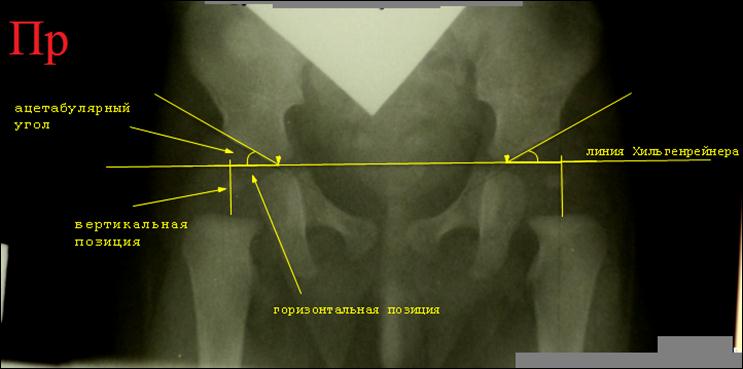

Начинают

расчерчивание с базовой линии Хильгенрейнера: проводят горизонтальную линию,

касающуюся нижних краев теней подвздошной кости. Затем проводят линии,

касательные к крышам вертлужных впадин, или линии крыш вертлужных впадин. Для

каждого сустава отмечают две точки: точка контакта линии Хильгенрейнера с

нижним краем тела подвздошной кости и точка на верхнем крае вертлужной впадины.

Соединяя точки, проводят линию крыши впадины. Угол между линией Хильгенрейнера

и линией крыши впадины называется ацетабулярным углом, у детей 3 месяцев он

должен быть 30° или меньше. Он отражает достаточность глубины впадины: чем он

меньше, тем впадина глубже.

На

верхнем конце рентгеновского изображения бедренной кости четко прослеживается

почти горизонтальная площадка. Это окостеневшая часть нижнего полушария головки

бедренной кости. На площадке надо найти середину и отметить точку, которая

является примерным центром головки бедра. Затем отмеченную точку соединяют перпендикуляром

с линией Хильгенрейнера. Длина отрезка от линии Хильгенрейнера до центра

головки бедра будет вертикальной позицией головки бедренной кости, она должна

быть не менее 10 мм. Расстояние от точки пересечения перпендикуляром линии

Хильгенрейнера до точки её контакта с нижним краем подвздошной кости будет

горизонтальной позицией головки бедренной кости, она должна быть не более 10

Снимок

нормальных тазобедренных суставов ребенка 3 месяцев, расчерчивание по схеме

Хильгенрейнера. Ацетабулярные углы с обеих сторон равны 28°, вертикальная и латеральные позиции головки бедра с

каждой стороны равны. Присмотревшись, вы можете заметить формирующиеся ядра

окостенения головок бедра с обеих сторон.